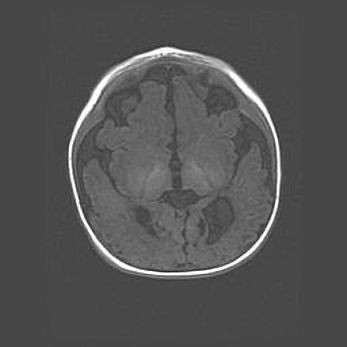

Лейкомаляция с кистозно-глиозной дегенерацией головного мозга.

Возраст: 2 месяца 25 дней

Вес: 6400 г

Окружность головы: 40 см

Срок гестации: 41 неделя

Лейкомаляцию относят к ишемически-гипоксическим повреждениям головного мозга, диагностируемым у новорожденных. При лейкомаляции в головном мозге обнаруживают очаги некроза, возникшие после тяжелой гипоксии и нарушения кровотока. В процессе морфогенеза очаги проходят три стадии: 1) развития некроза, 2) резорбции и 3) формирования глиозного рубца или кисты. Перивентрикулярная лейкомаляция (ПЛ) встречается примерно в 12% случаев среди новорожденных, обычно – у недоношенных детей, причем, частота ее зависит от массы, с которой младенец появился на свет. Наибольшее число малышей страдает лейкомаляцией, если масса при рождении 1500-2500 г.